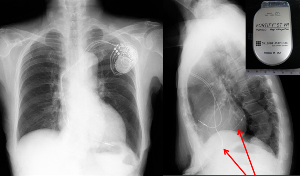

具体的には左心室の前後にペースメーカーのリード(→)を留置し、左心室を挟み込むような形で心臓を動かす治療です。

日本Medtronic社提供2017年9月1日よりMedtronic社®️ MICRA™️によるリードレスペースメーカを導入予定です。この技術革新により皮下ポケットや電極リードが不要になります。ペースメーカのトラブルの8割はポケット感染やリード断線に起因するものですので、それを克服できると考えております。

100円玉との比較ではいかに小さいデバイスかがお判りいただけるかと思います。